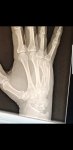

I know this is a bit "how long is a piece of string type question" but I strained/sprained my hand/thumb just over two weeks ago and I'm still struggling to hold a club.

Swelled up quite badly initially but that has subsided and it's definitely getting better, I pretty much have full use of my hand for every day duties (ooh err missus) but the swinging of a stick with a weight on the end is causing me pain, mainly in the back of the hand and I'm getting impatient.